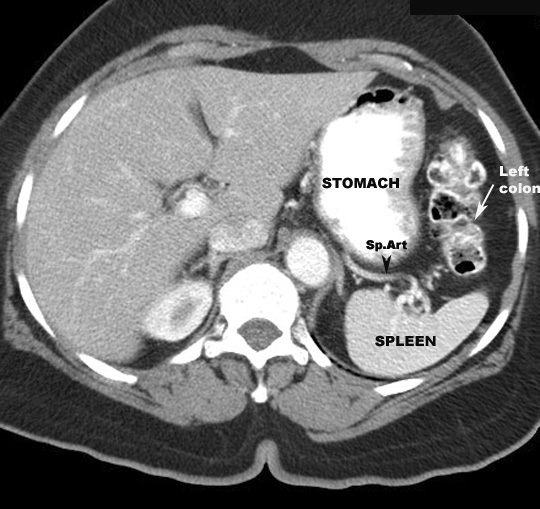

Splenic flexure

- Attached to diaphragm by phrenico-colic

ligament

- Related to

- spleen

- Tail of pancreas

- Left kidney